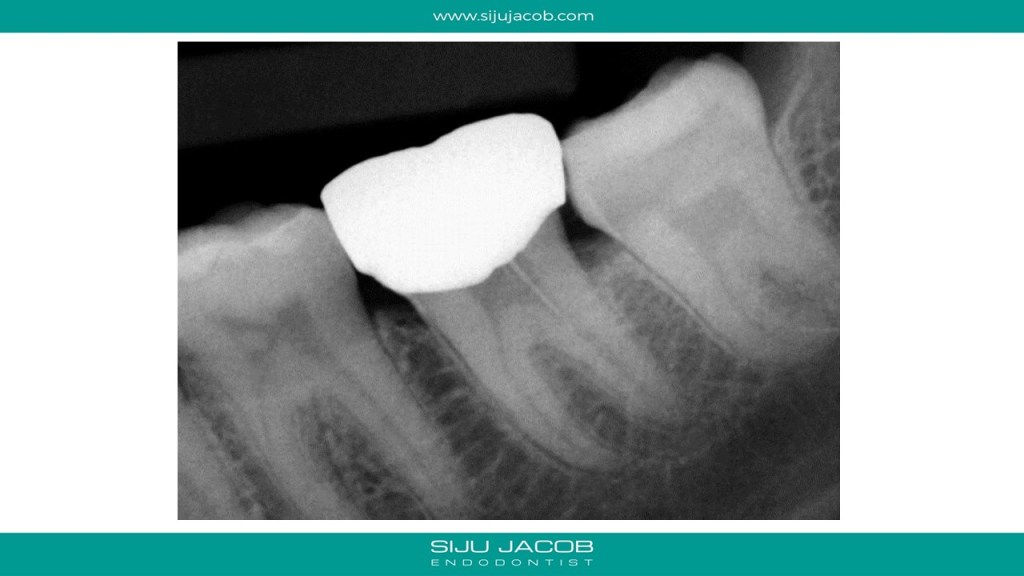

This was a bizarre case. Patient came from another state to Bangalore for a wedding. Came to the clinic with acute pain. She said that she had endo and crown done the previous week. She told me that the doctor who treated her used a microscope and also showed her pictures of three canals filled. I told her that on the radiograph, it looked liked her dentist had attempted to fill one canal. She was quite sure that she saw pictures of three canals filled. I removed the crown, reopened the access cavity and to my surprise found gutta percha mesially. It was in the periodontal ligament!